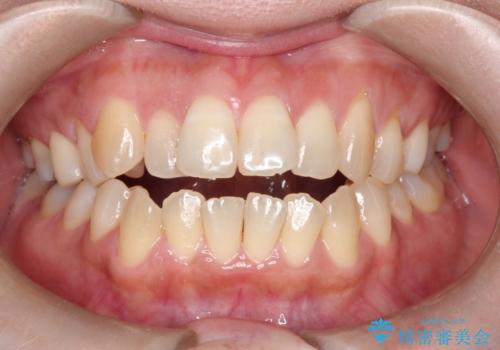

[ インビザライン ] 目立たないマウスピース矯正で、前歯のがたつきをきれいにしたい

担当医 大元洋佑

![[ インビザライン ] 目立たないマウスピース矯正で、前歯のがたつきをきれいにしたいの症例 治療前](https://seimitsushinbi.jp/wp/wp-content/uploads/2024/04/IMG_3912-500x350.jpg?v=1711960039)

![[ インビザライン ] 目立たないマウスピース矯正で、前歯のがたつきをきれいにしたいの症例 治療後](https://seimitsushinbi.jp/wp/wp-content/uploads/2024/04/cd64e6566cc0683feee2abf20f8241f9-500x350.jpg?v=1711960118)